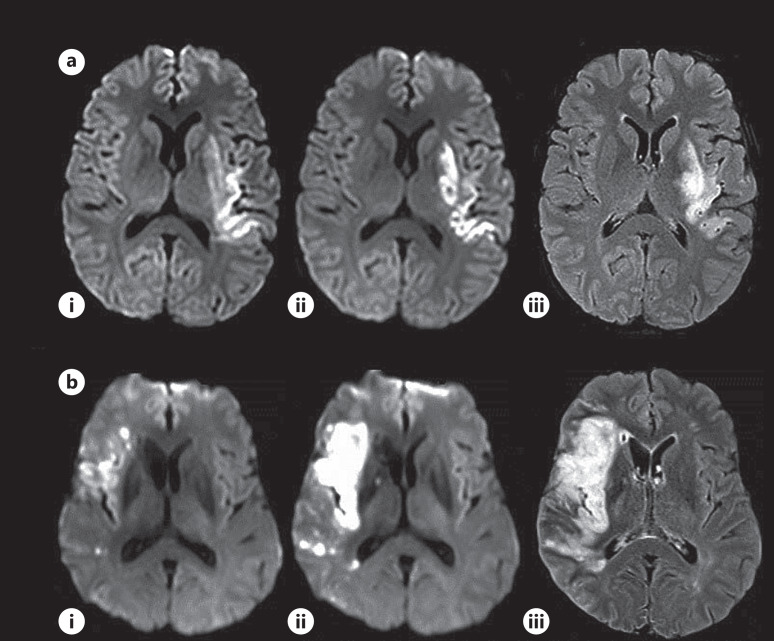

导言 MRI 或 CT 上的卒中病灶体积提供了缺血性卒中导致组织损伤的客观证据。多项研究已将血管内治疗(EVT)后 24 小时的 "最终 "病灶体积测量作为临床预后的替代指标。然而,尽管血管再通术取得了成功,但仍有相当一部分患者的临床疗效并不理想。本研究的目的是量化治疗后第一周的病灶生长情况,确定早期预测因素,并探讨与临床预后的关系。方法 这是一项前瞻性研究,研究对象是两个中心符合以下标准的卒中患者:i)前方大血管闭塞(LVO)急性缺血性卒中;ii)尝试过 EVT;iii)EVT 后 24 小时和 5 天内进行过 3T MRI 检查。我们将 "早期 "和 "晚期 "病变增长分别定义为基线与 24 小时 DWI 之间以及 24 小时 DWI 与 5 天 FLAIR 之间病变增长≥10 毫升。完全再灌注的定义是:在EVT前和EVT后24小时之间,灌注延迟(Tmax>6秒)的组织体积减少>90%。30天或90天后的改良Rankin量表(mRS)为0-2,即为良好的临床结果。结果 112名患者符合研究标准,中位年龄67岁,56%为女性,中位NIHSS 19,54%接受了静脉或IA溶栓治疗,66%为M1闭塞,中位基线DWI体积21.2毫升。87%的患者成功再通,68%的患者完全再灌注,总体临床预后良好率为53%。近三分之二(65%)的患者没有出现晚期病变生长,24 小时至 5 天之间的中位体积变化为-0.3 毫升,相关的临床预后良好率也很高(64%)。然而,约有三分之一的患者(35%)尽管成功实现了再通畅,但其晚期病变仍有显著增长(87%:46% mTICI 2b/ 41% mTICI 3)。晚期病变增长患者的晚期病变体积变化为 27.4 毫升,早期病变体积变化为 30.1 毫升。这些患者的出血转化率增加了 68%,每 3 名患者中仅有 1 人的临床结果良好。晚期病灶增长与不完全再灌注、出血转化和不良预后密切相关。结论 EVT 术后,大约每 3 名患者中就有 1 人出现晚期病灶增生,其中每 3 名患者中只有 1 人的临床预后良好。大多数早期病灶没有生长的患者晚期病灶也没有生长。识别晚期病灶生长的患者对指导临床治疗和 EVT 后的预后至关重要。此外,它还可以作为一种成像生物标志物,用于开发减轻再灌注损伤的辅助疗法。

Methods: This is a prospective study of stroke patients at two centers who met the following criteria: (i) anterior large vessel occlusion acute ischemic stroke, (ii) attempted EVT, and (iii) had 3T MRI post-EVT at 24-h and 5-day. We defined "early" and "late" lesion growth as ≥10 mL lesion growth between baseline and 24-h diffusion-weighted imaging (DWI) and between 24-h DWI and 5-day fluid attenuated inversion recovery imaging, respectively. Complete reperfusion was defined as >90% reduction of the volume of tissue with perfusion delay (Tmax>6 s) between pre-EVT and 24-h post-EVT. Favorable clinical outcome was defined as modified Rankin scale (mRS) of 0-2 at 30 or 90 days.

Results: One hundred twelve patients met study criteria with median age 67 years, 56% female, median admit NIHSS 19, 54% received IV or IA thrombolysis, 66% with M1 occlusion, and median baseline DWI volume 21.2 mL. Successful recanalization was achieved in 87%, and 68% had complete reperfusion, with an overall favorable clinical outcome rate of 53%. Nearly two-thirds (65%) of the patients did not have late lesion growth with a median volume change of -0.3 mL between 24-h and 5-day and an associated high rate of favorable clinical outcome (64%). However, ∼1/3 of patients (35%) did have significant late lesion growth despite successful recanalization (87%: 46% mTICI 2b/41% mTICI 3). Late lesion growth patients had a 27.4 mL change in late lesion volume and 30.1 mL change in early lesion volume. These patients had an increased hemorrhagic transformation (HT) rate of 68% with only 1 in 3 patients having favorable clinical outcome. Late lesion growth was independently associated with incomplete reperfusion, HT, and unfavorable outcome.